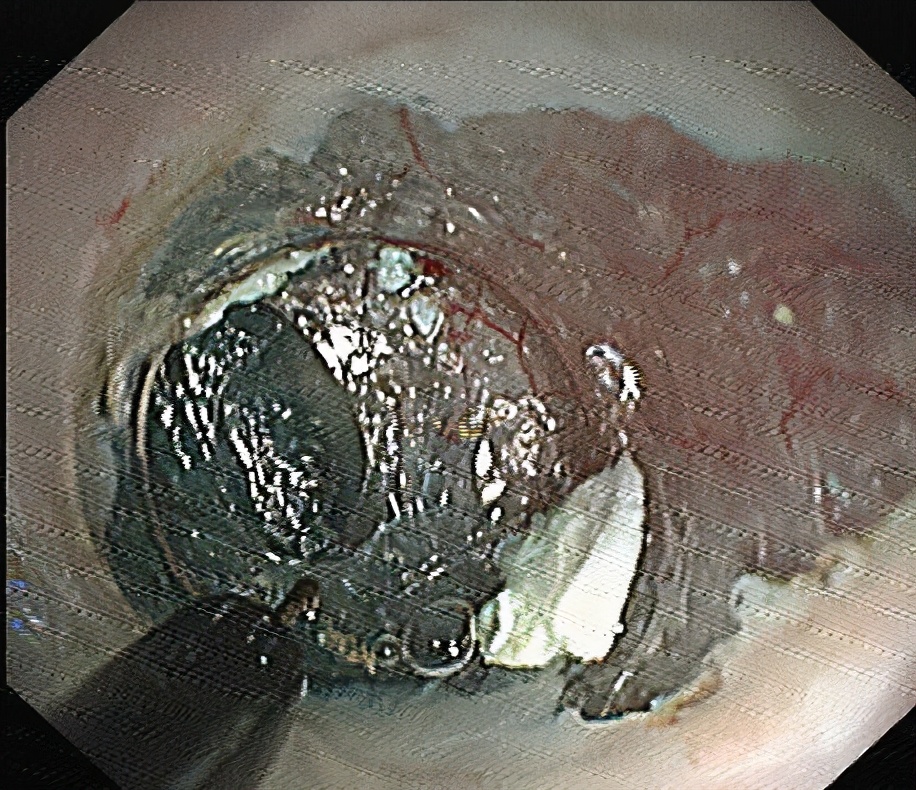

04

环形肌切开。

05

退出“隧道”前观察,钛夹关闭黏膜层切口。